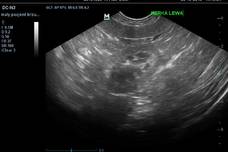

Dla naszych pacjentów przygotowaliśmy ambulatorium oraz małą salę operacyjną. Pomieszczenia zapewniają najwyższy poziom świadczonych usług i pełen komfort podczas zabiegów. Poczekalnia zapewnia miły pobyt w czasie oczekiwania na wizytę.